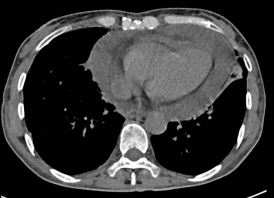

近日,一位肿瘤晚期的老年女性患者因并发急性心包填塞,被紧急送往广元市第一人民医院心胸血管外科就诊。入院时,患者已出现严重呼吸困难、心力衰竭等症状,剧烈的胸闷与濒死感让她痛苦不堪。检查显示,肿瘤转移引发的大量心包积液已对心脏形成致命压迫,若不及时解除压迫,患者随时可能因心跳骤停死亡,生命危在旦夕。

然而,患者处于肿瘤晚期,身体耐受度极差,还因年事已高合并多种基础疾病,给治疗带来了巨大挑战。传统治疗需采用全麻手术,需气管插管、机械通气辅助,不仅手术创伤大、术后并发症风险高,更可能因麻醉应激导致病情急剧恶化,甚至引发术中猝死。经综合评估,患者手术风险等级评估为极高危,传统治疗方案难以实施。

面对“治则风险极高、不治则即刻致命”的两难困境,市第一人民医院心胸血管外科副主任陈均带领团队迅速开展多学科会诊,结合患者病情特点与技术优势,果断决定采用Tubeless无管化胸腔镜心包开窗引流术。这一创新技术无需气管插管、无需留置导尿管,无需使用肌松剂,通过“三无”微创模式从根源上降低手术创伤与并发症风险,尤其适合老年体弱、危重疑难患者。

手术当天,陈均团队与麻醉科紧密协作。麻醉科张莉副主任、刘兴红医师在超声引导下精准区域神经阻滞,配合短效镇静镇痛药物,确保患者在自主呼吸状态下平稳接受手术。术中,陈均团队通过单孔胸腔镜精准定位心包积液区域,仅以微小切口完成开窗引流操作,快速排出压迫心脏的积液,成功解除了致命性心脏压迫。整个手术过程视野清晰、操作精准高效,在最大限度保障患者安全的同时,将手术创伤降至最低。